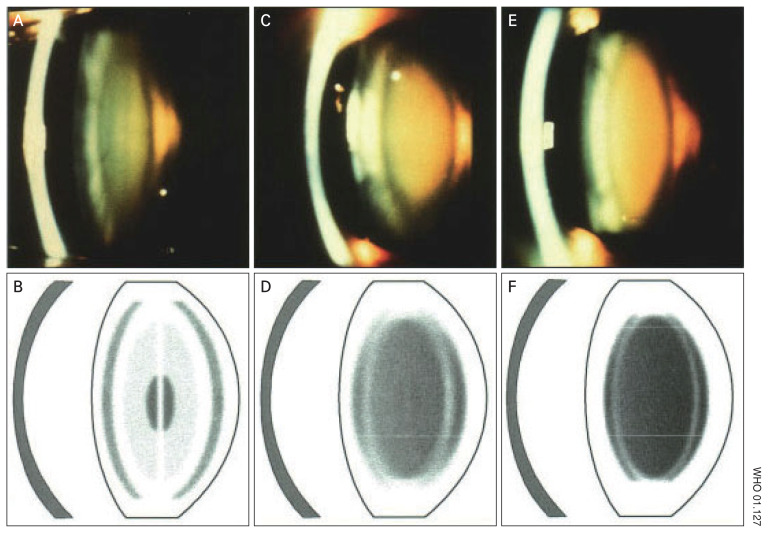

Purpose: Cataracts are the cause of more than 50% of blindness in the world. Cataract is diagnosed using a slit lamp to evaluate the opacity of the lens. Slit lamps as the primary tools cataract are not available in primary care units. Smart Eye Camera (SEC) is a medical device placed on smartphone, capable of creating slit beam similar to conventional slit lamp. Previous studies have been conducted in Japan. We wanted to further compare ocular examination between SEC and conventional slit lamp with samples taken from UPTD Eye Clinic Ambon Vlissingen in Indonesia.

Methods: Observational analytical study with a cross-sectional study design. The research sample consisted of 67 people selected by consecutive sampling. All samples were examined for cataracts using a conventional slit lamp and SEC. To evaluate the accuracy of SEC, diagnosis of cataract was carried out by one observer based on slit-lamp images. The results of examinations were then compared with the examinations by two observers based on the SEC video, where the videos were read two times in a span of 1 week.

Results: Sixty-seven eye samples were taken with average age of 61.76 ± 5.83 years, visual acuity was 0.07 ± 0.12, intraocular pressure was 14.12 ± 2.06 mmHg, and SEC video duration was 4.15 ± 1.09 seconds. SEC intraobserver reliability has a κ of 0.795/0.818, SEC interobserver reliability has a κ of 0.795/0.817. SEC assessment accuracy for observer 1 has a κ of 0.606/0.681 and for observer 2 has a κ of 0.629/0.717, with the highest accuracy for cataract grade 3 (86.67% and 91.18%, respectively).

Conclusions: This study shows SEC has good consistency and reliability in assessing the degree of nuclear cataract compared to conventional slit lamp. This tool could be used for cataract screening in remote areas.